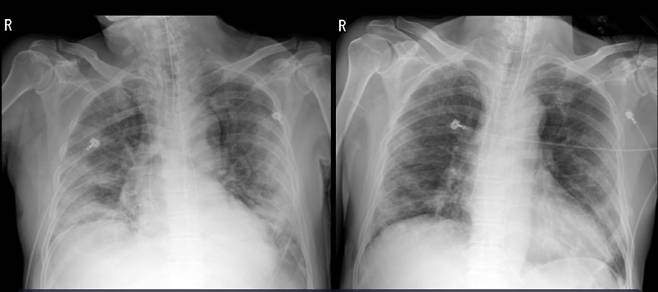

연구팀은 완치 판정을 받고 2주가 지난 남성의 회복기 혈장 500ml를 김씨에게 12시간 간격으로 두 번에 걸쳐 투여했고, 동시에 스테로이드 치료도 시작했다. 혈장치료와 스테로이드 치료를 받은 김씨의 경우 열이 떨어지고 CRP는 5.7mg/L로 정상범위로 떨어졌다. 흉부 X-ray 검사상 양쪽폐도 더 이상 나빠지지 않았다. 혈장을 투여받는 동안 특별한 부작용도 없었다. 현재 김씨는 인공호흡기를 제거했고, 코로나19 검사에서 음성 반응으로 완치 판정을 받았다.

이씨의 경우 역시 완치자의 회복기 혈장을 12시간 간격으로 두 번에 걸쳐 투여했다. 혈장 투여와 스테로이드 치료를 시행한 후 림프구수가 회복되고 바이러스 농도가 감소했다. 흉부 X-ray 검사에서 폐의 침윤이 몰라보게 좋아졌으며, CRP 역시 정상 수준을 회복했다. 이씨는 이후 완치 판정을 받고 3월 말 퇴원했다.